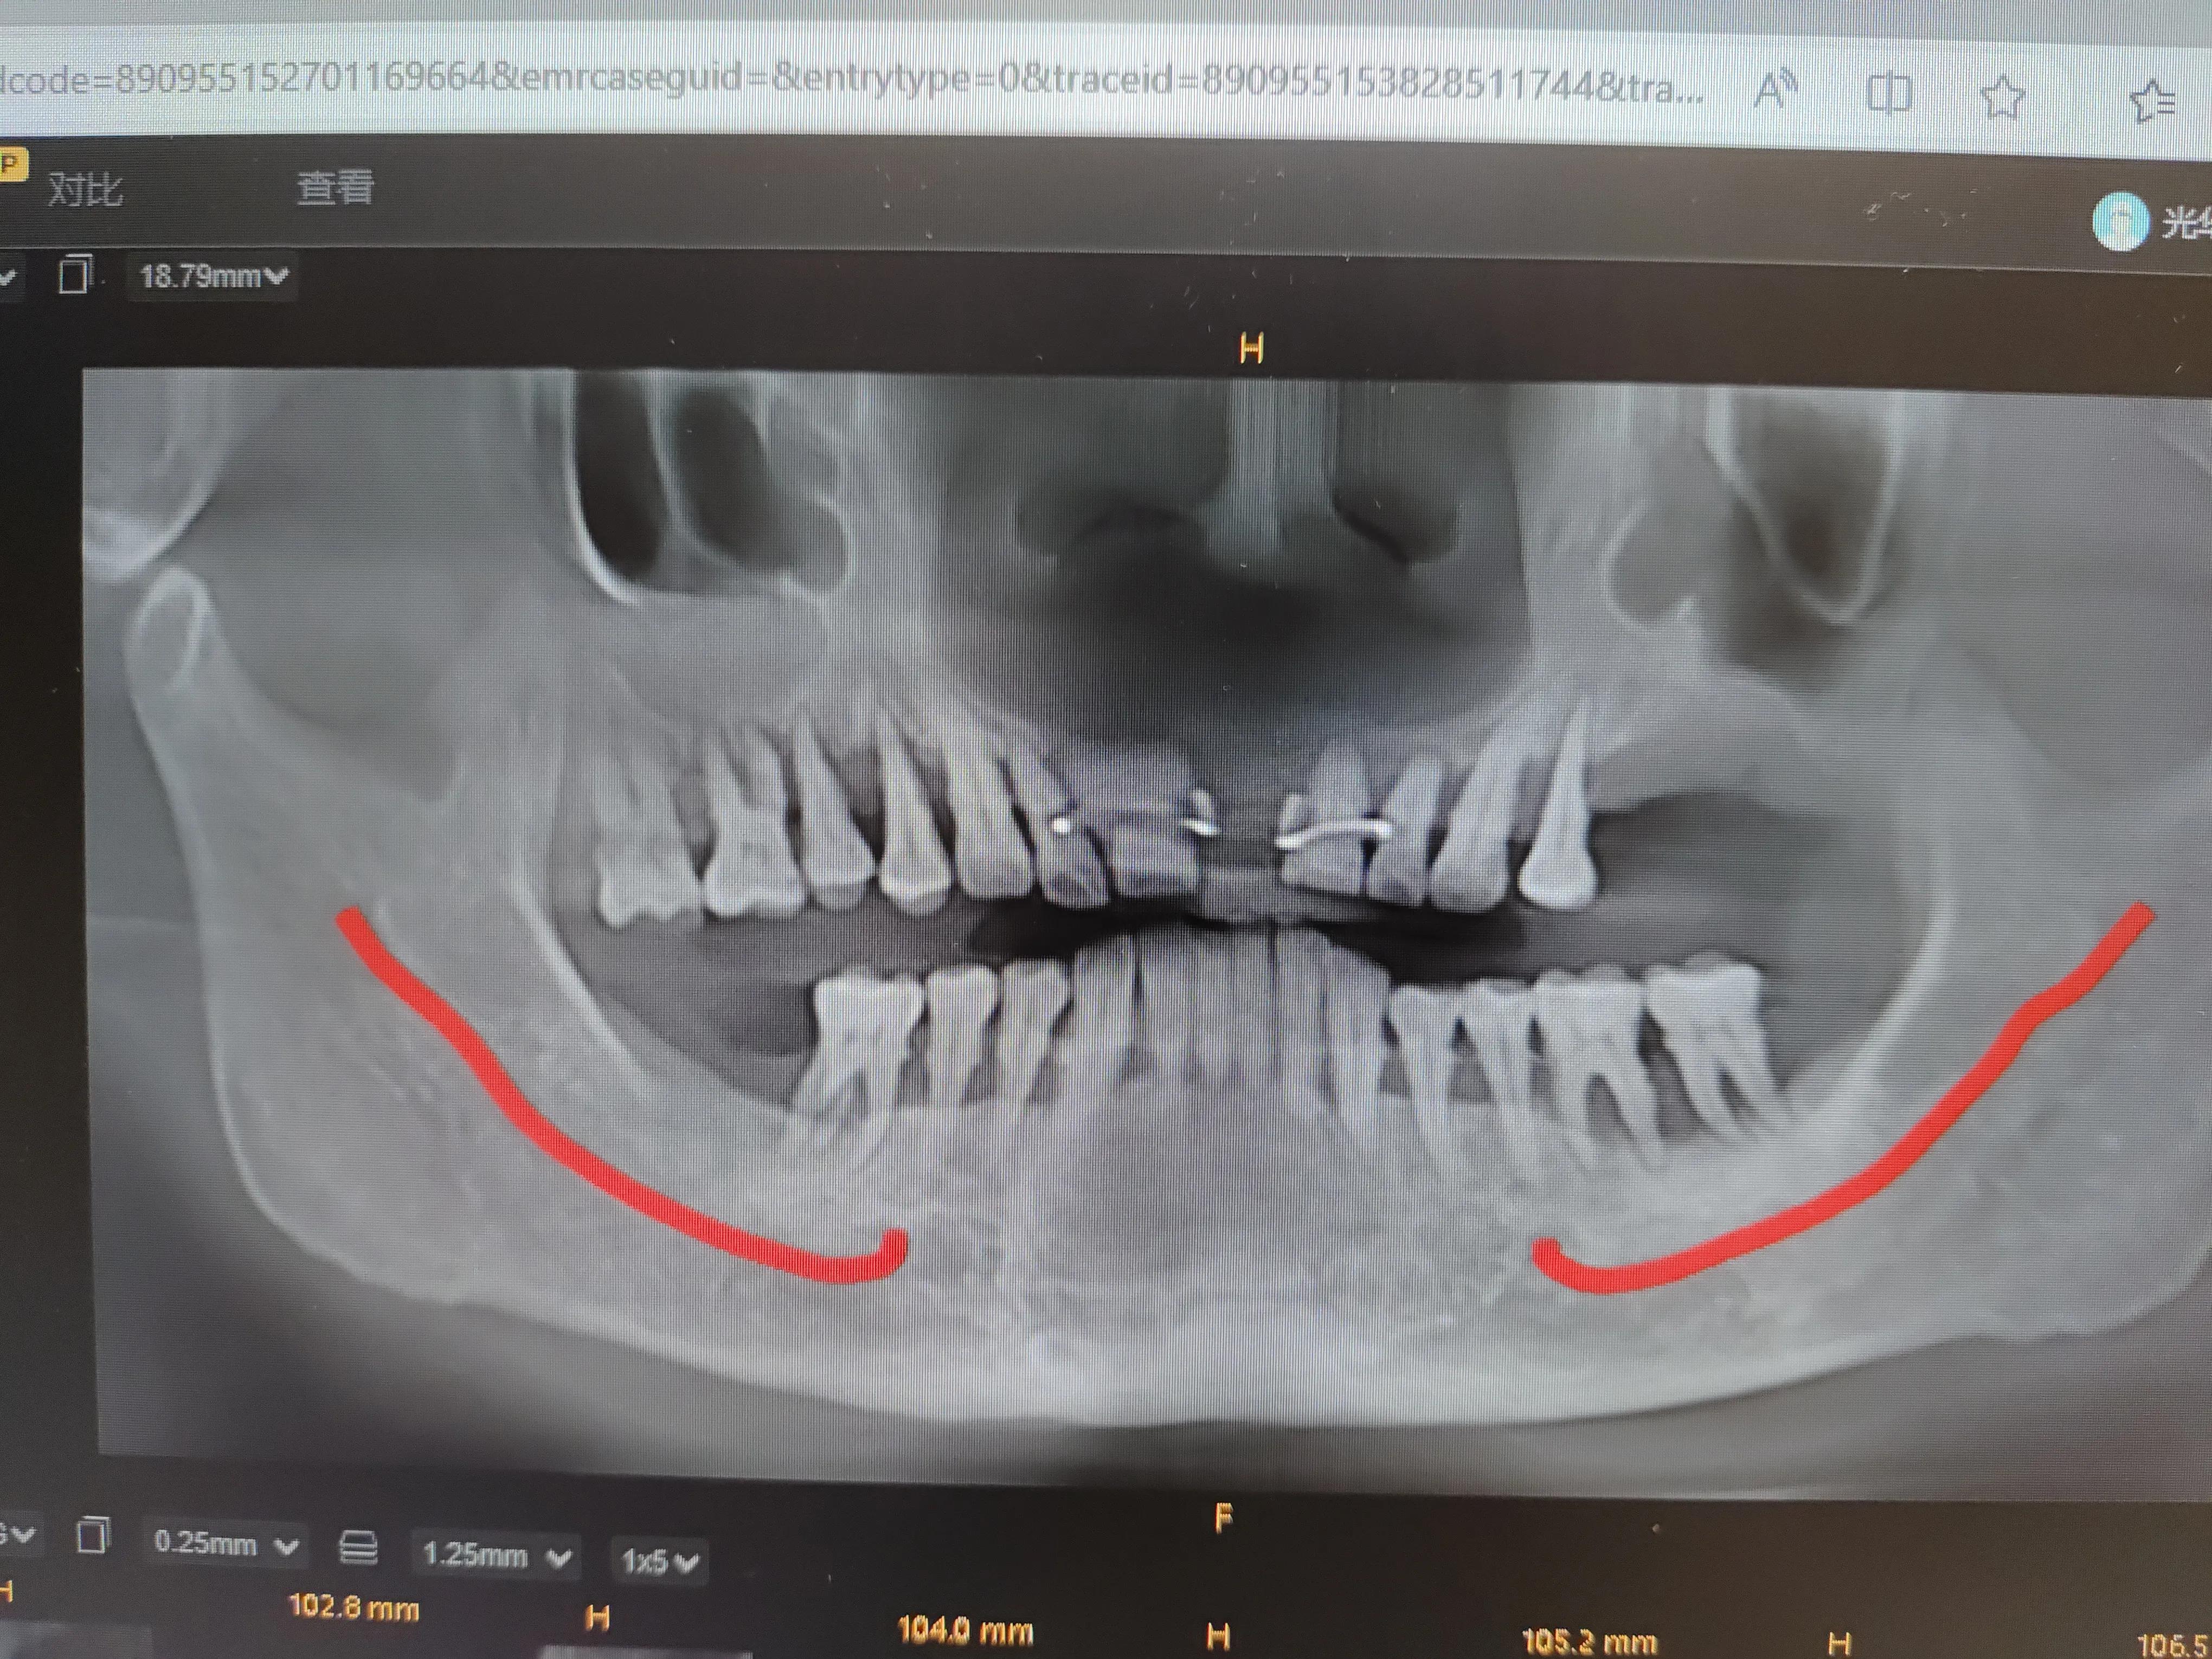

我牙齿拍的CT

我的牙龈萎缩厉害